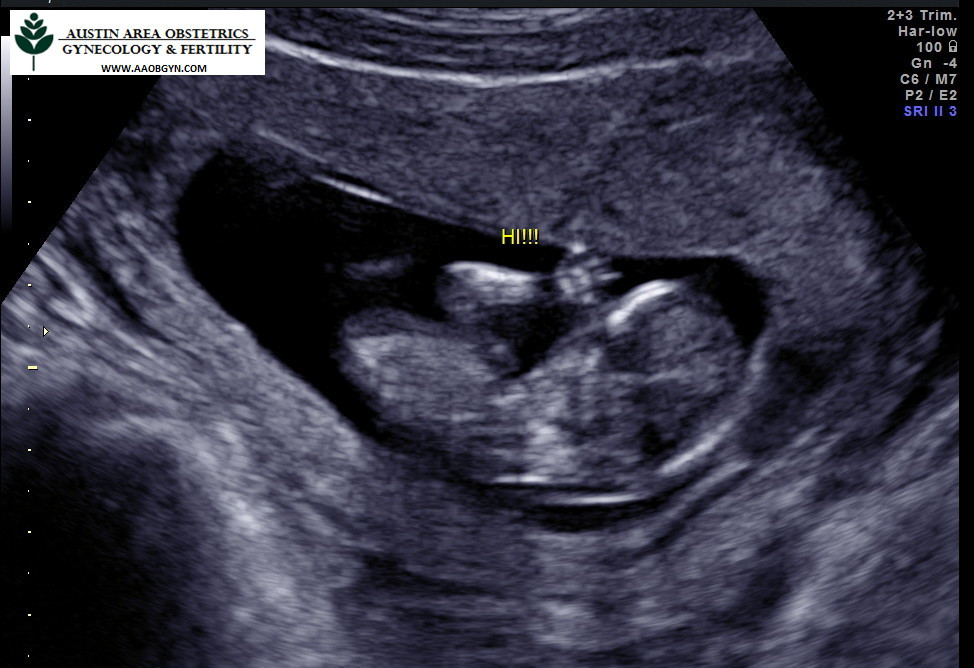

12주차

꼬물거리는 뱃속의 오스틴을 확인하고 왔다. 뱃속에서 딸꾹질도 하고 손발도 움직이는걸 보면 어찌나 귀여운지! 벌써 기관이 거의 다 생겨 엄지공주같이 사람 모습하고 있는게 너무 신기했다. 소화불량은 계속되고 살이 1키로 넘게 쪘다. 미국에서는 이 시기에 염색체검사나 유전자검사를 추가로 더하면 성별을 알 수 있다고 하는데 하지 않았다. 20주까지 기다리면 자연적으로 알게 될텐데 뭐. 건강한 태아가 더 중요하다. 1차 기형아검사를 무사히 통과했다.